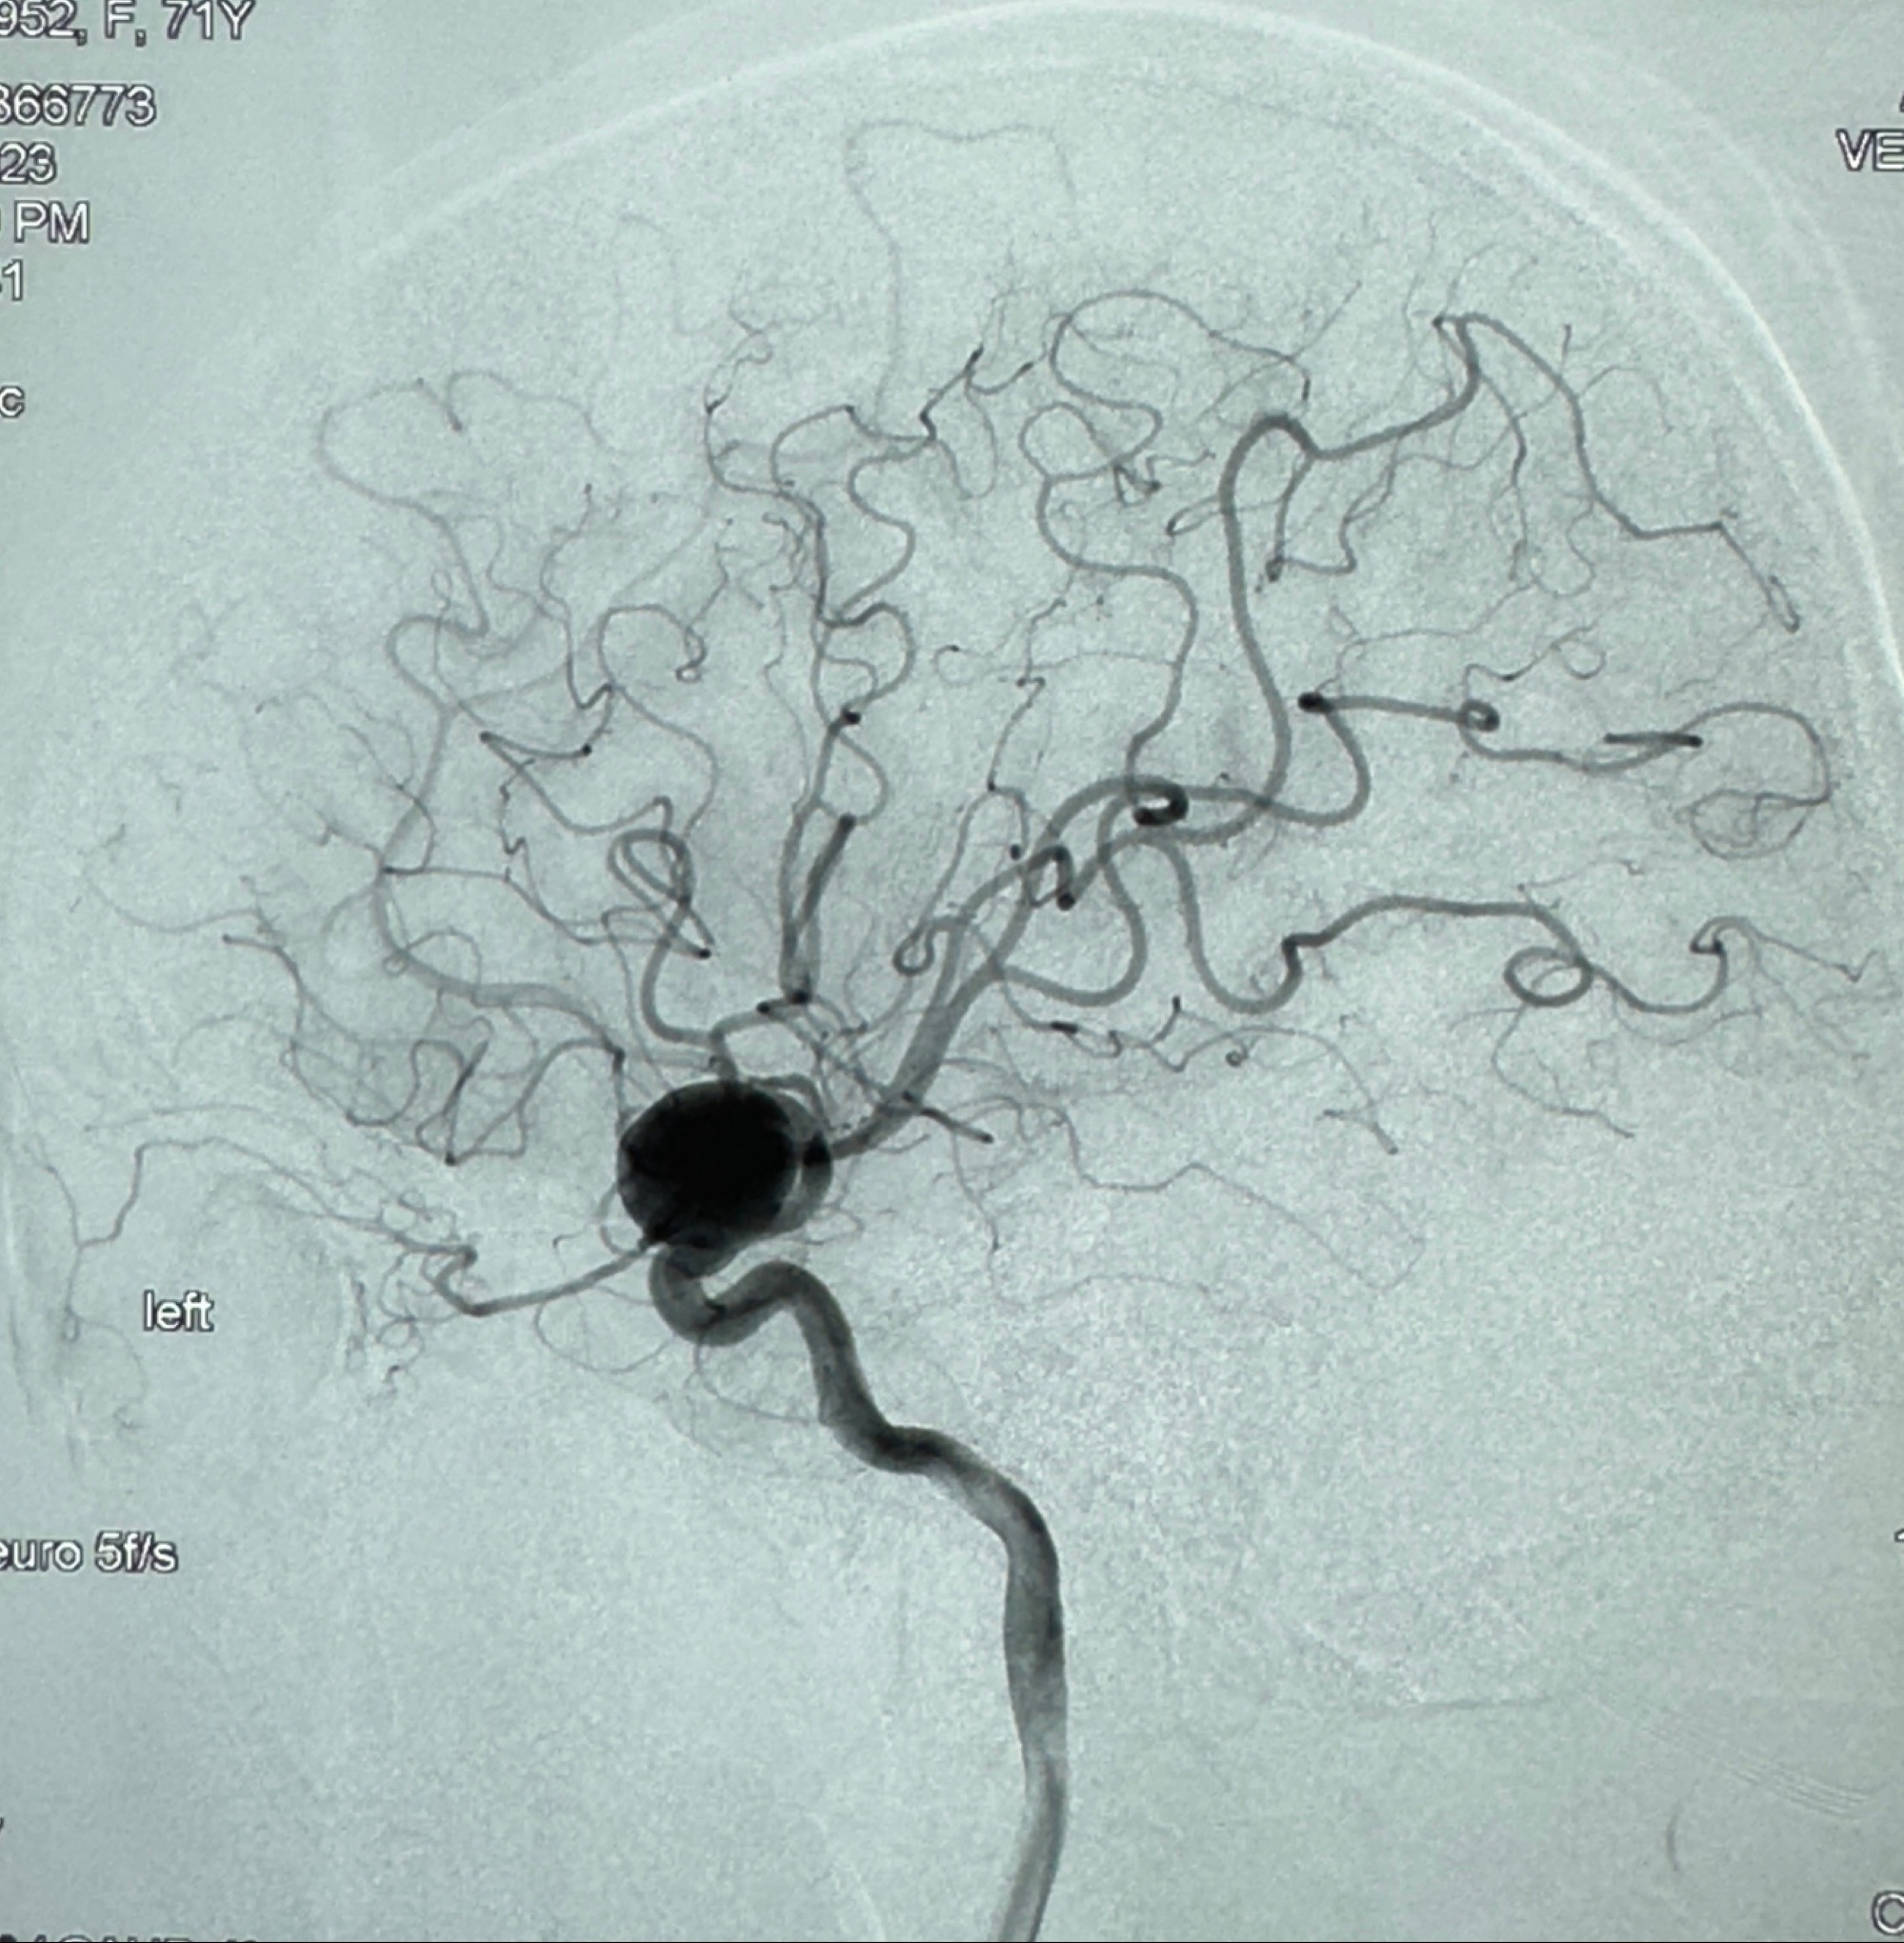

现病史:患者诉2年来反复发作性头痛,顶枕部为主,因自己考虑高血压可能,未予系统检查;患者约20日前无明显诱因下突发剧烈头晕,有天旋地转感,不能睁眼,伴视物模糊;外院查头颅MRI+MRA提示:左侧颈内动脉C6段动脉瘤;遂至复旦大学附属华山医院就诊,于2023-12-08行全脑血管造影提示:右侧颈内动脉C6段动脉瘤,瘤颈6.68mm,动脉瘤大小13.28*12.34mm,建议行密网支架辅助栓塞术治疗,因缺乏相关材料遂出院。现患者仍有顶枕部头痛不适,为求进一步诊疗脑血管病变至我科就诊,收治入院。

2023-12-08 复旦大学附属华山医院 全脑血管造影:右侧颈内动脉C6段动脉瘤,瘤颈6.68mm,动脉瘤大小13.28*12.34mm

初步诊断:1.右侧颈内动脉眼动脉段动脉瘤

2023-12-08外院DSA:右侧颈眼动脉瘤,约13*12mm大小,压颈试验显示左右向及后向前代偿可